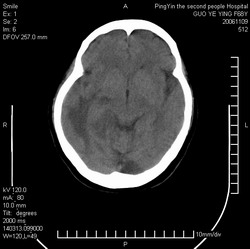

郭*,61岁 ,头痛半月并有复视

右侧颞枕叶见形态不规则等密度灶,灶周可见水肿灶,考虑:1、胶质瘤?2、转移瘤?建议做增强或mri检查

右侧颞枕叶见形态不规则等密度灶,中心见低密度影,灶周可见水肿明显,右侧脑室受压变窄,考虑胶质瘤或转移瘤。请作增强或mri检查

平扫观察右侧至少有3个结节伴周围水肿,首先考虑转移。先查肺部吧。

右侧颞枕叶示结节状影,外缘示片状低密度影,相应脑室未见明显受压,考虑转移瘤。

右侧脑实质内多发结节影并指状水肿.

意见:考虑多发转移瘤.

右侧颞枕叶见多个形态不规则等密度灶,中心见低密度影,灶周可见水肿明显,右侧脑室受压变窄,考虑转移瘤或胶质瘤。请作增强或mri检查